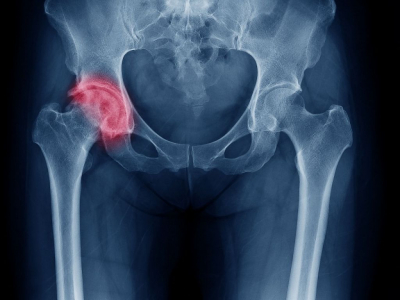

Inflamație a articulației șoldului, care cauzează durere și mers șchiopătat, sinovita de șold poate să apară la orice vârstă, dar este întâlnită în special la…